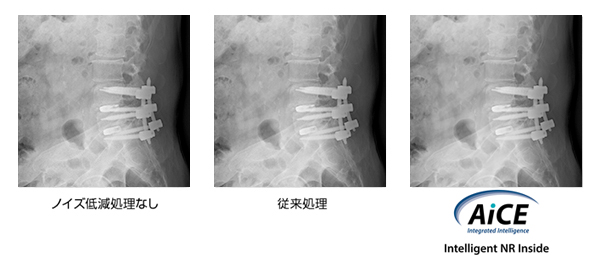

Deep Learningを用いたノイズ低減処理AiCE,Intelligent NR Inside

Deep Learningを応用して大量の臨床データを学習させることで,高性能なノイズ低減を実現するニューラルネットワークモデルを形成。鮮鋭度の維持と粒状性の改善を両立する高画質な診断画像を提供します。